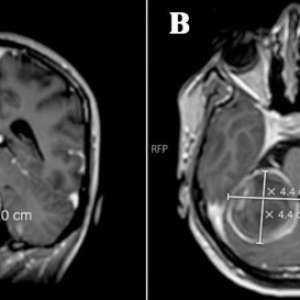

Огромная аневризма у беременной

Беременная, 23 года

Настоящая беременность вторая, на 28-й неделе обратилась к врачу с жалобами на периодические головные боли, которые значительно усилились за последние три дня. Головная боль стала невыносимой, отдавала в шею и сопровождалась многократной рвотой и выраженной светобоязнью.

Примечательно, что после рождения первого ребёнка два года назад она была госпитализирована на месяц из-за постоянных головных болей и лихорадки, МРТ головного мозга не выполнялось. До недавнего времени её текущая беременность протекала без осложнений.

У пациентки не было в анамнезе гипертонии, диабета или заболеваний соединительной ткани. Она не принимала никаких препаратов и не употребляла алкоголь и табак.